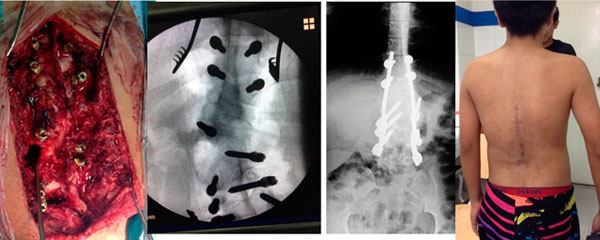

Paciente de 1 año y 8 meses con escoliosis congénita progresiva, se realizo resección de hemivertebra con colocación de tornillos transpediculares.